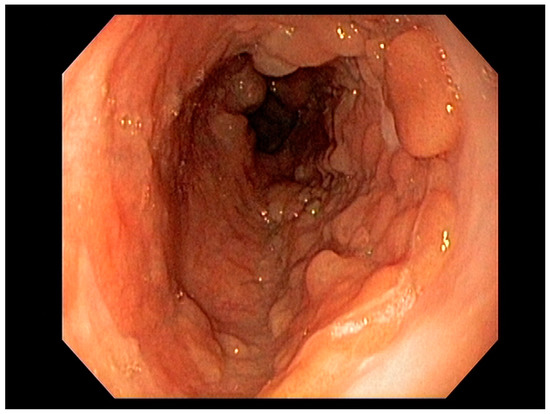

4.2. Early Gastric Cancer (EGC)

4.3. Endoscopic Ultrasound in Staging of Gastric Cancer

- Waddingham, W.; Nieuwenburg, S.A.V.; Carlson, S.; Rodriguez-Justo, M.; Spaander, M.; Kuipers, E.J.; Jansen, M.; Graham, D.G.; Banks, M. Recent advances in the detection and management of early gastric cancer and its precursors. Front. Gastroenterol. 2020. [Google Scholar] [CrossRef]